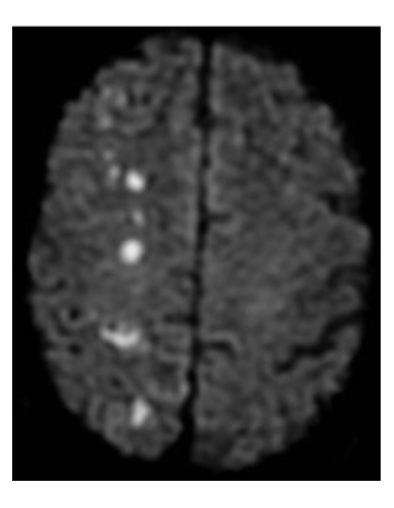

23

Q

What territory is impacted in the provided DWI/

A

MCA superior division territory

The provided DWI image is indicative of what etiological cause of stroke?

watershed or thrombotic stroke